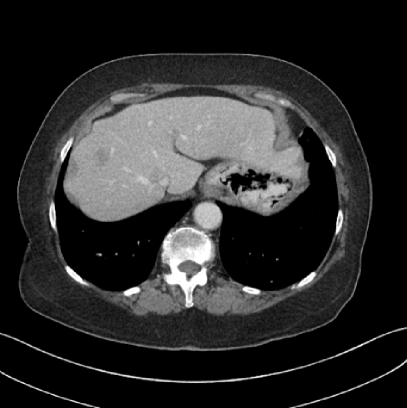

Refer to caption

(a) Clinical Standard Hybrid IR

(b) JENG

Figure 15: An example cross-plane image from the same thoracic dataset as in Fig. 14. (a) A coronal-view image slice of the clinical standard hybrid IR in soft tissue window. (b) JENG at a comparable resolution but with reduced image noise and artifacts.